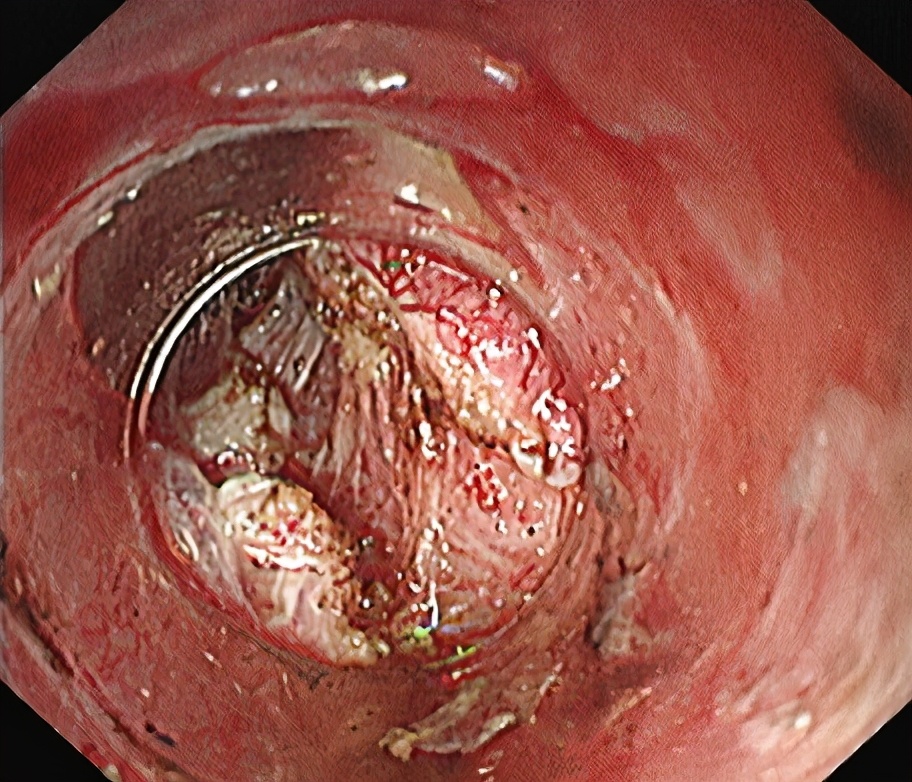

食管粘膜层切开。

分离粘膜下层,建立黏膜下“隧道”。

环形肌切开。